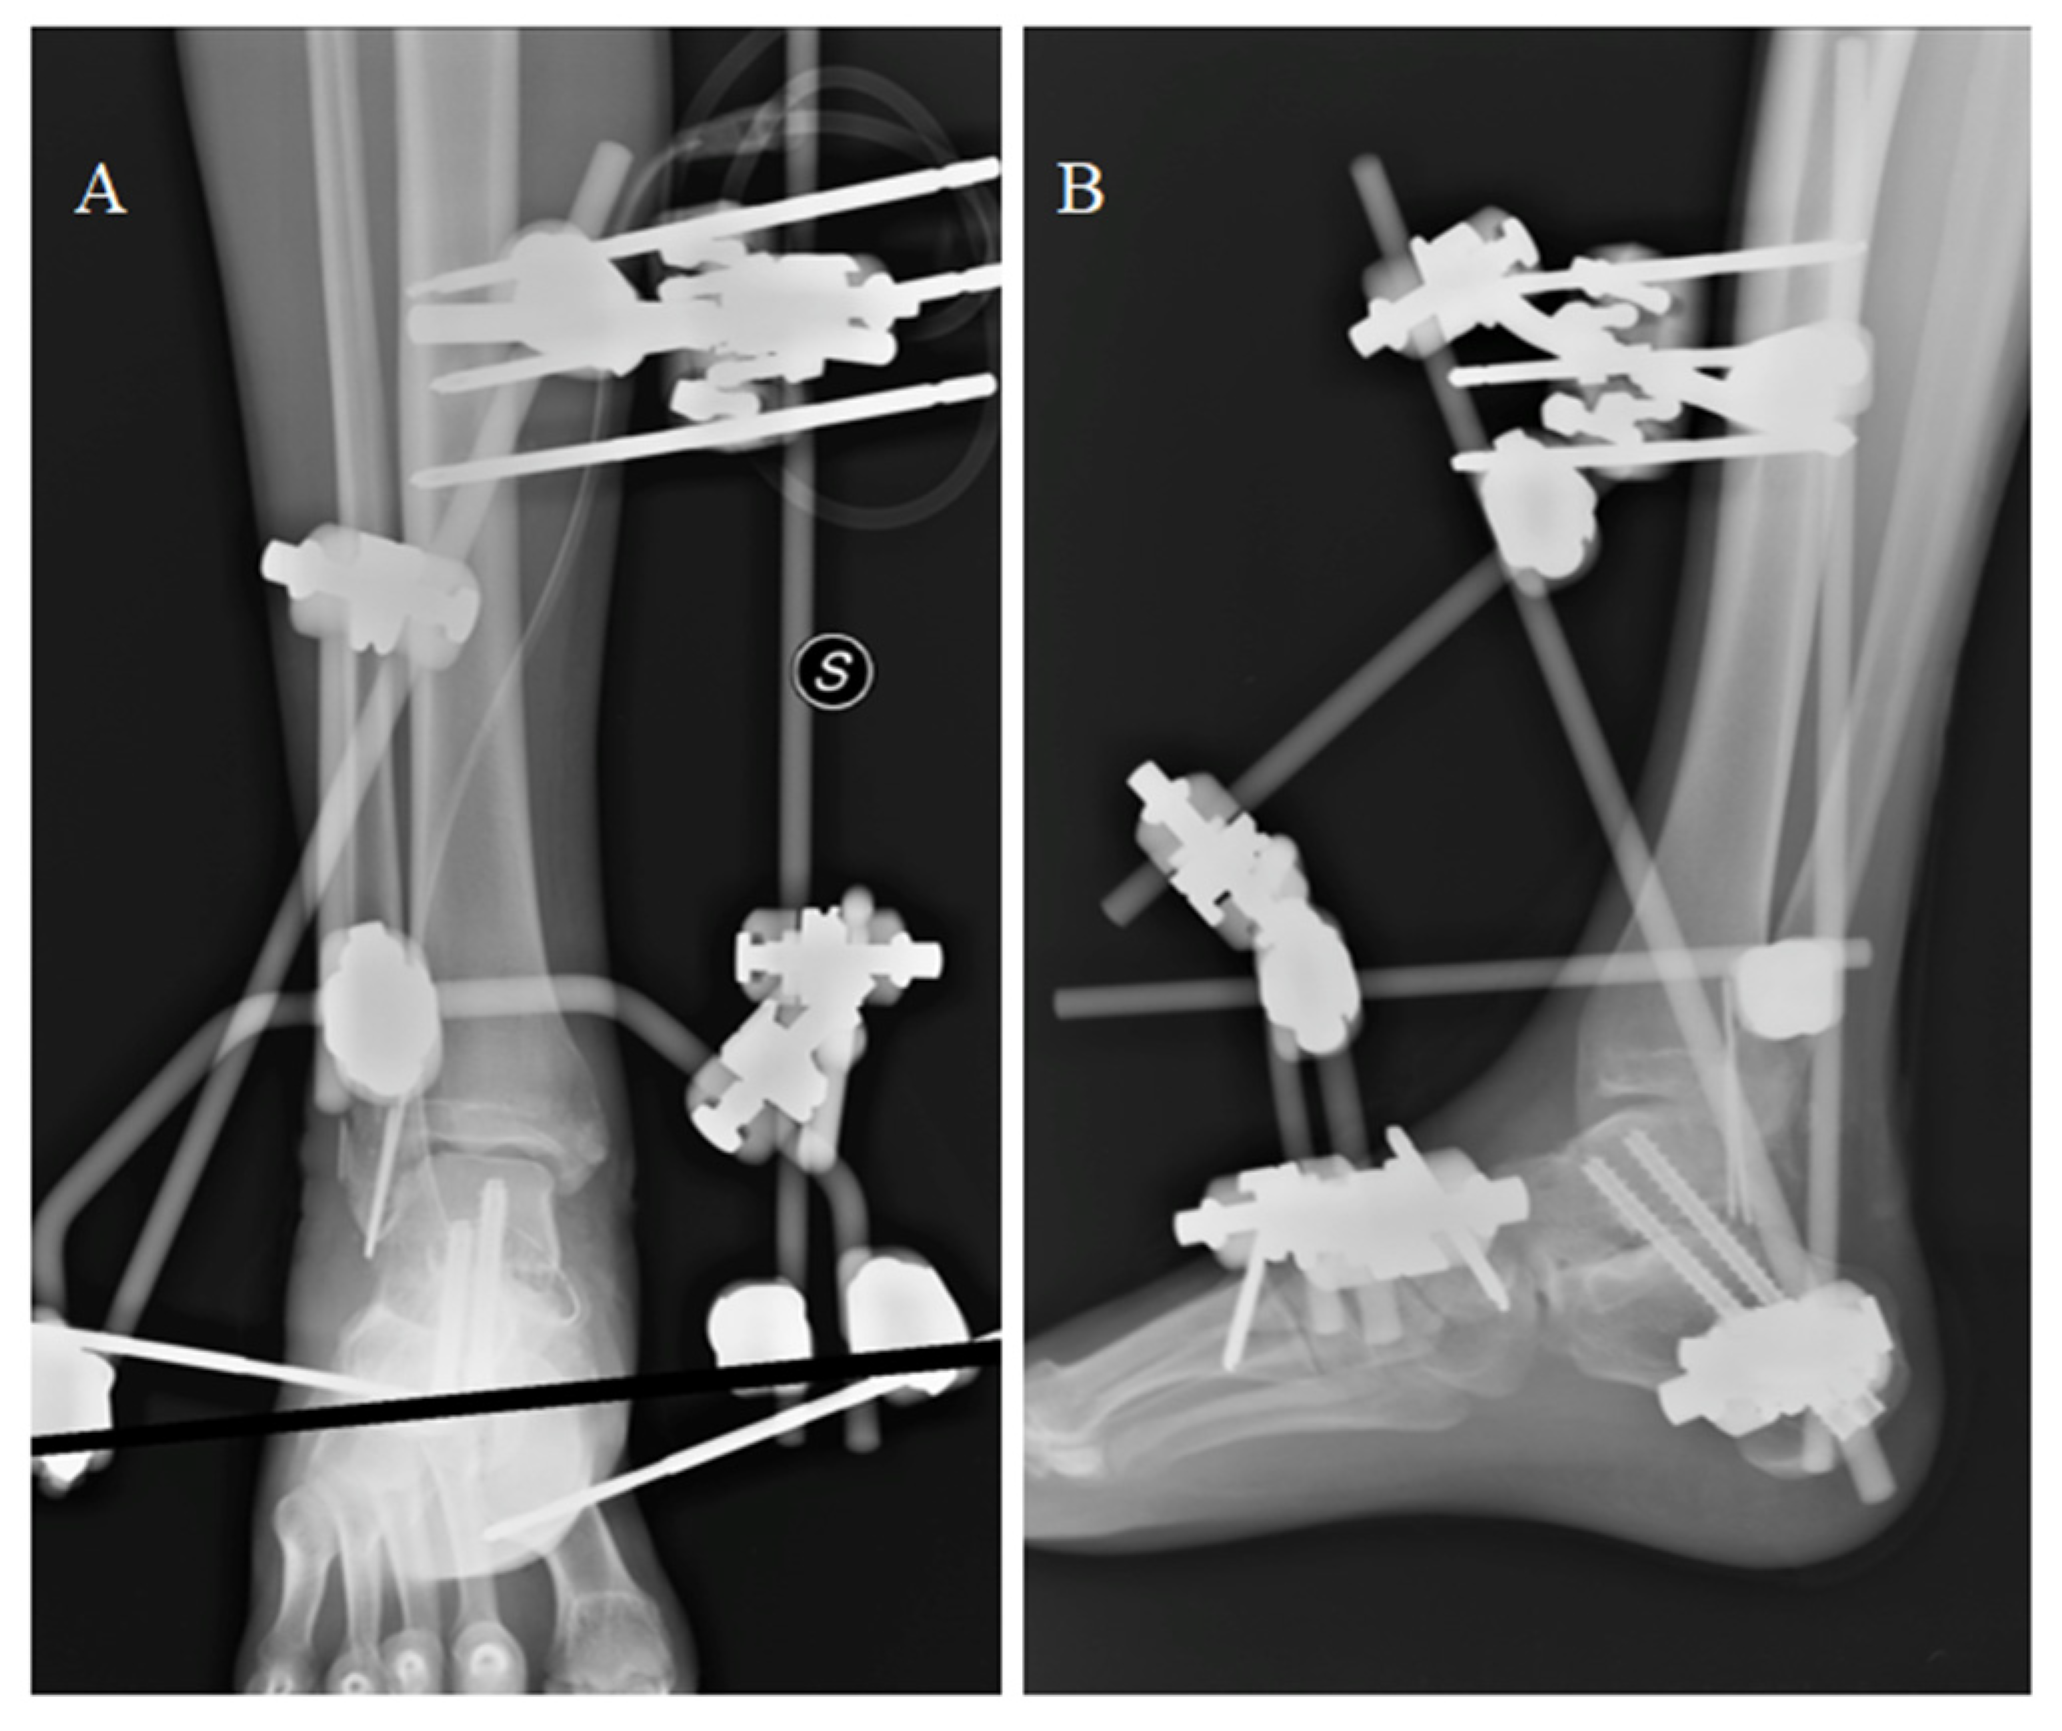

Four channels were carved at the level of the talus neck to fit the screws and allow ligament reconstruction. Two months after the accident, the prosthetic replacement and ligament reconstruction was finally performed by exposing the cement spacer through an anteromedial longitudinal approach. After cement removal, a customized guide was used to prepare the upper surface of the calcaneal bone according to preoperative planning. The talar prosthesis was fixed to the calcaneus by two screws. Antero-medial capsule-ligamentous reconstruction was performed using a peroneus brevis tendon allograft inserted at the level of the talus foramen and stabilized at the tibial level with a transosseous tunnel and Soft Tissue Anchoring System (CONMED) (Figure 8).

Figure 8.

The prosthesis ready to be implanted (A). X-ray of the implant from antero-posterior (B) and latero-lateral (C) projections. Articular space can be observed in figure (B).

After surgery, the ankle was immobilized in a plaster cast for 3 weeks. At 6 weeks, the patient started gait re-education with progressive weight bearing and a bivalve brace. In 12 weeks, the patient started walking without any limitations. At 1 year follow-up, good radiographic results and a fair functional outcome were reported (AOFAS = 74; NRS = 2); total ROM was 30° with 10° of dorsiflexion and 20° of plantar flexion.